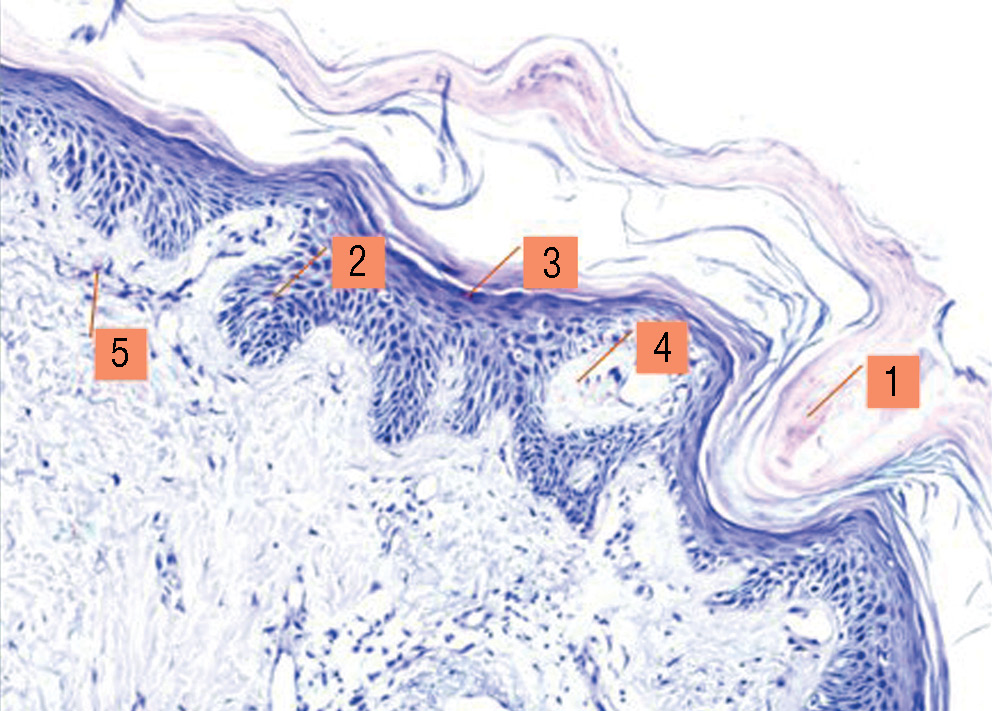

Результат первого гистологического исследования (рис. 1) характеризовался гиперплазией эпидермиса, гиперкератозом, присутствием и некоторым утолщением зернистого слоя эпидермиса, расширением капилляров сосочков дермы, присутствием воспалительного инфильтрата в дерме, состоящего исключительно из лимфоцитов и моноцитов, что позволило предположить диагноз «питириаз красный волосяной отрубевидный» (рис. 2).

Рис. 1. Гистологическое исследование биоптата кожи, окраска гематоксилином и эозином (× 200): 1 — фолликулярный гиперкератоз, расширенный волосяной фолликул; 2 — слабовыраженный неравномерный акантоз; 3 — сохраненный зернистый слой; 4 — отек сосочков дермы; 5 — периваскулярный лимфогистиоцитарный инфильтрат

Fig. 1. Histological examination of a skin biopsy, stained with hematoxylin and eosin (× 200): 1 — follicular hyperkeratosis, enlarged hair follicle; 2 — mild uneven acanthosis; 3 — granular layer preserved; 4 — edema of the dermal papillae; 5 — perivascular lymphohistiocytic infiltrate